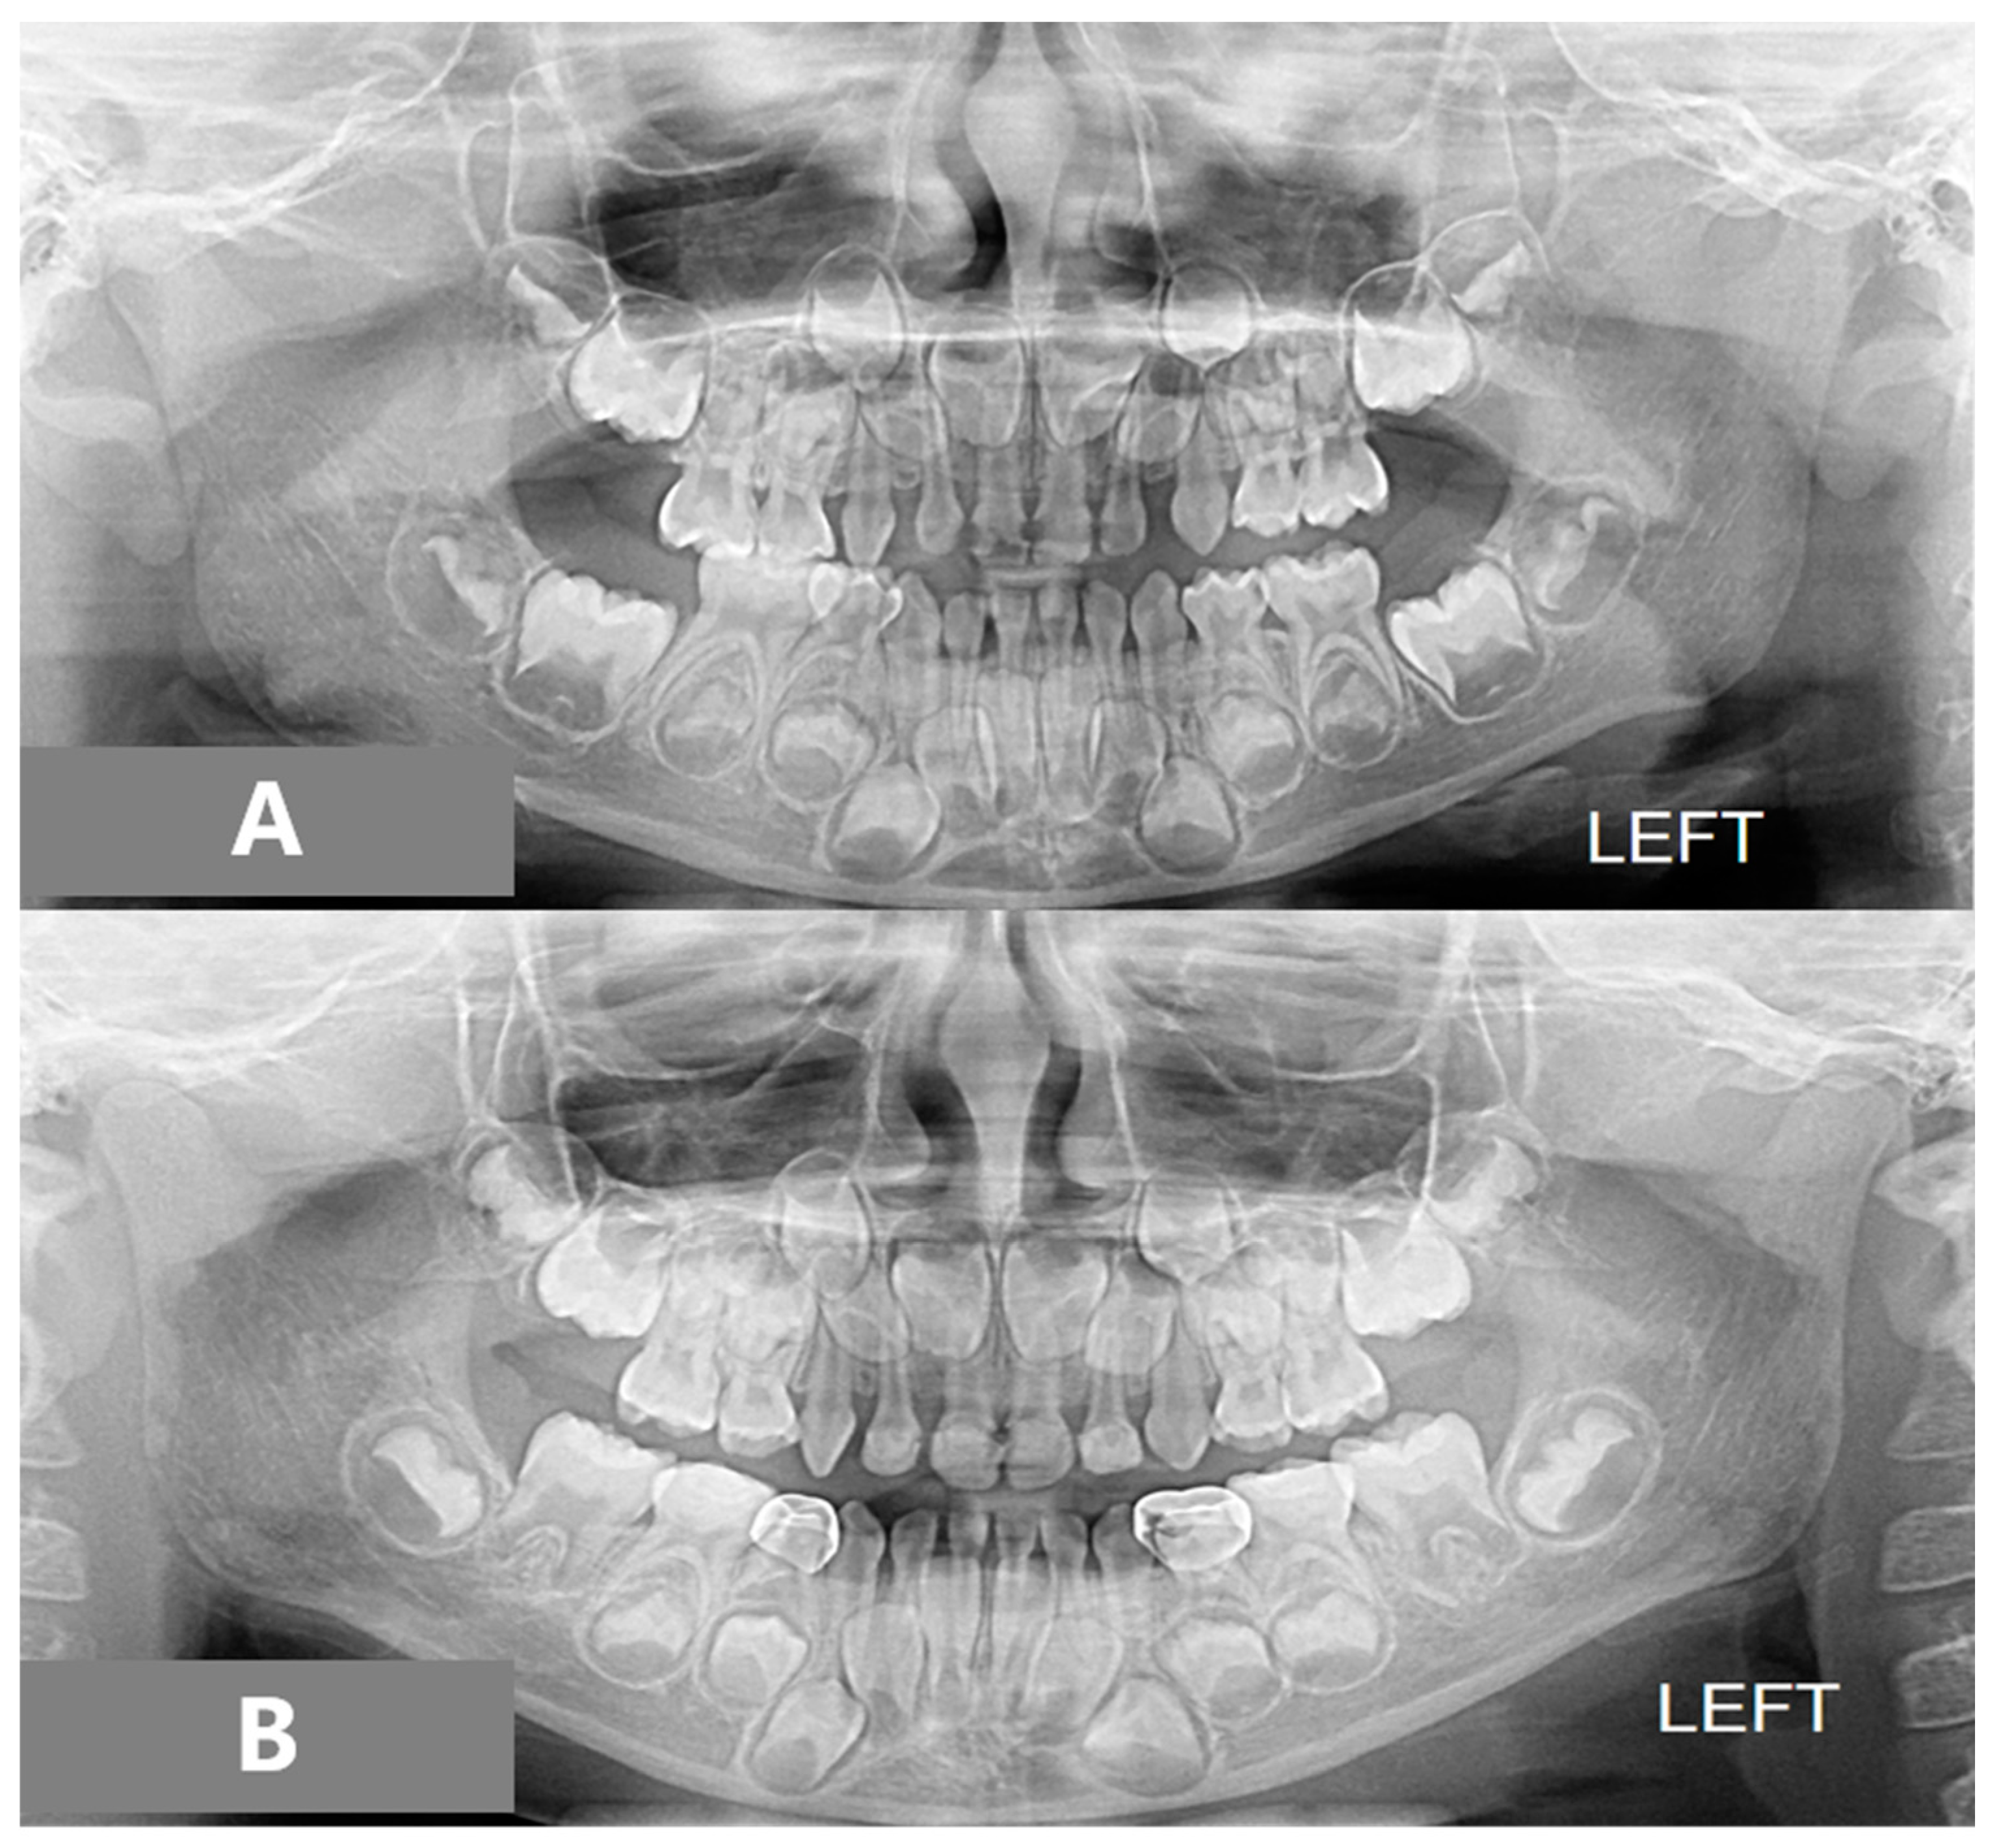

After 11 months of active treatment, the crossbite of the anterior teeth and the unilateral scissor bite on the right side were successfully corrected (Figure 3). The pre-treatment and post-treatment lateral cephalographs and panoramic radiographs are presented in Figure 4 and Figure 5. The pre-treatment and post-treatment lateral cephalometric data are presented in Table 1.

Figure 4.

Panoramic radiographs: (A) pre-treatment, (B) post-treatment.